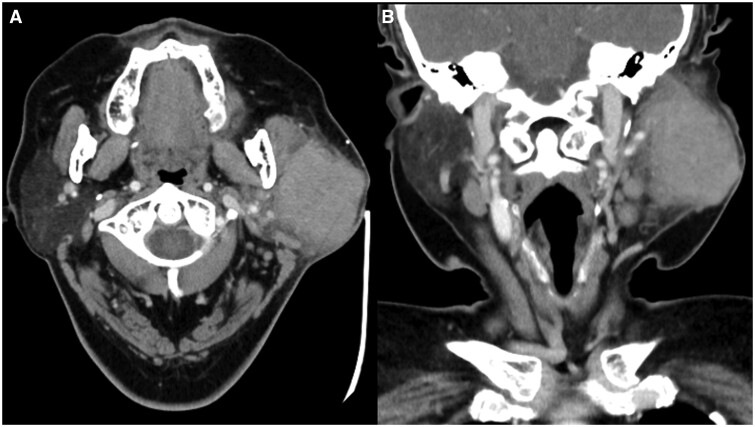

The authors present the case of a 59-year-old lady diagnosed with lymphoepithelial carcinoma (LEC) of the left parotid gland. The primary tumour was identified using contrast-enhanced CT, and diagnosis was confirmed via fine needle aspiration cytology and immunohistochemistry. Staging using fluorine-18 fluorodeoxyglucose PET CT revealed regional nodal metastases, while no distant metastasis was evident. Following radical radiotherapy, a favourable locoregional response was observed on MRI, yet the patient's plasma Epstein-Barr virus load continued to rise. Given her primary tumour's somatostatin receptor type 2 (SSTR2) positivity, gallium-68 DOTA-[Tyr3] octreotate PET CT (68Ga-DOTATATE PET CT) was performed, revealing multiple distant metastases with DOTATATE avidity. Despite attempts at palliative chemotherapy and immunotherapy, disease progression led to the decision for the best supportive care. The unique presentation of metastatic LEC on 68Ga-DOTATATE PET CT suggests a potential role for SSTR2-targeted imaging in diagnosis and management.